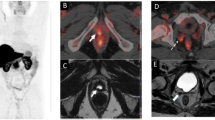

The possibility of using radiolabeled copper [Cu(ATSM)] and ionic Cu(II) salts for PET imaging of tumor has also been demonstrated in clinical studies with different cancer types, including lung, cervical, rectal, head and neck, brain, and prostate cancer. One of the reasons these cancer types were chosen in the studies with [*Cu][Cu(ATSM)] PET imaging is because of the difficulties to detect hypoxia due to the physical inaccessibility to use invasive methods [30,31,32,33]. Although the exact mechanism and relations to tissue hypoxia explaining the retention of either [64Cu][Cu(ATSM)] or ionic copper-64 is yet to be identified, the benefits of using these PET tracers have been demonstrated clinically. For instance, Dietz et al. demonstrated the effectiveness of [60Cu][Cu(ATSM)] as a predictor of neoadjuvant chemoradiotherapy response and survival of patients with rectal cancer [34]. More recently, it has been reported that radiolabeled copper [*Cu][Cu(ATSM)]/[*Cu]CuCl2 can be used as a predictor of radiotherapy response in head and neck cancer ([62Cu][Cu(ATSM)]) [35], staging and detection of recurrent prostate cancer ([64Cu]CuCl2) [36, 37], and imaging of brain tumors ([64Cu]CuCl2) [38]. A summary of clinical studies with either copper-labelled ATSM or ionic radiocopper is shown in Table 1.

These clinical studies have demonstrated the possibility of using radiolabeled copper [*Cu][Cu(ATSM)]/[*Cu]CuCl2 for PET imaging of solid tumors and potentially for hypoxia imaging. In addition, therapy response and overall survival may be possible to predict with the aid of tissue-to-muscle ratios. Compared to [18F]-FDG, radiolabeled copper [*Cu][Cu(ATSM)] have been able to selectively image heterogeneity in tumor hypoxia within the tumor mass [31, 33, 39,40,41]. Compared to fluorine-based hypoxic PET tracers such as [18F]-FMISO and [18F]-choline, radiolabeled copper [*Cu][Cu(ATSM)]/[*Cu]CuCl2 have the advantages of much faster pharmacokinetics, better signal-to-noise ratio, and no interference due to absence of urinary bladder uptake [36, 37, 42]. Furthermore, ionic [64Cu]Cu2+ have also demonstrated improved diagnostic sensitivity in a recent study involving 50 patients with prostate cancer, with 82% detection rate compared to 74% using multiparametric MRI, which is the standard radiologic procedure, and 56% using [18F]-choline-PET, although the authors did not report comparisons with the more recently developed prostate-specific membrane antigen (PSMA)-based PET tracer [37]. Despite early experiments were mainly based on radiolabeled copper [*Cu][Cu(ATSM)], later studies have also involved ionic radiocopper and reached similar results. Notably, if the copper retention indeed followed solely the ligand-based trapping mechanism, using ionic radiocopper should not cause any selective accumulation in hypoxic tumors. Combining the clinical and in vivo preclinical results, it is clear that copper itself also plays an important role in the hypoxic selectivity and therefore should be emphasized.